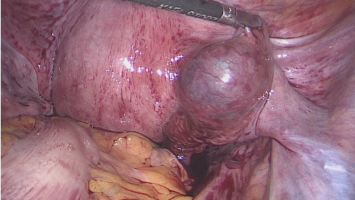

Operative Konzepte für die Therapie der Endometriose

Die operative Therapie der Endometriose ist anspruchsvoll. Sie reicht von der Resektion oberflächlicher peritonealer Herde bis zur interdisziplinären Operation mit partiellen Organresektionen an Darm, Blase, Urogenitaltrakt und Zwerchfell. Die …

Infertilität bei Endometriose – operieren oder gleich die künstliche Befruchtung?

Entzündungen im veränderten Peritonealraum sowie Endometriosezysten beeinträchtigen die Ovarien und mindern die Eizellqualität – mit erhöhtem Risiko für Fehlgeburten. Zwei Therapiepfade stehen zur Wahl: Operation oder assistierte Reproduktion. Doch während die eine Methode zunehmend kritisch betrachtet wird, gewinnt die andere immer mehr an Bedeutung.

Endometriose und Kinderwunsch – wann operieren, wann nicht?

Eine Operation kann auch bei Endometriose-Patientinnen mit unerfülltem Kinderwunsch der richtige therapeutische Schritt sein. Allerdings ist der optimale Zeitpunkt vom Stand der Familienplanung, Lebensalter und der bisherigen Vorgeschichte abhängig. Rein diagnostische Operationen sind obsolet und sollten idealerweise vermieden werden.